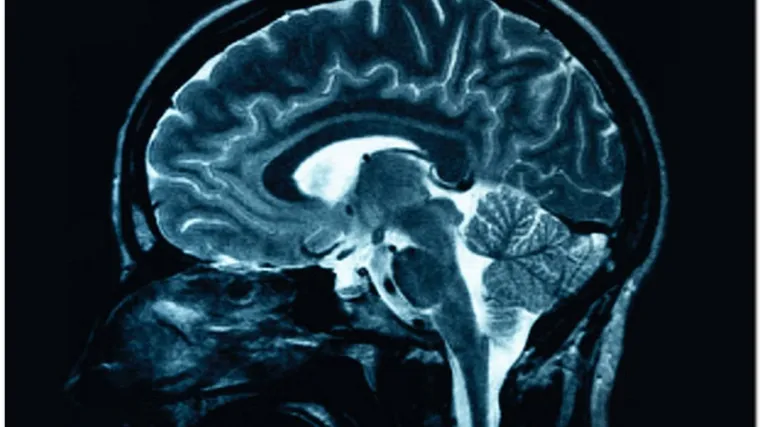

Poremećaji mozga skupo stoje Europu

Godišnja cijena poremećaja mozga u Europi skočila je na 798 milijarda eura, a kontinent se suočava s političkom, socijalnom i financijskom tempiranom bombom jer obolijeva sve više ljudi.

U studiji Europskog vijeća za mozak piše da će račun za moždane poremećaje poput depresije, tjeskobe, nesanice ili demencije rasti jer ljudi žive duže, pa te bolesti postaju glavni gospodarski izazov europskoga zdravstva. Projekcija tih troškova napravljena je nakon rujanskoga objavljivanja rezultata studije koja je otkrila da Europljani često pate od neuroloških i mentalnih poremećaja: gotovo 165 milijuna ljudi, ili 38 posto stanovništva svake godine boluje od moždanog poremećaja poput depresije, tjeskobe, nesanice ili demencije. U samo trećini slučajeva bolesnici dobivaju potrebnu terapiju ili lijekove i zato su mentalni poremećaji golem gospodarski i socijalni teret težak stotine milijarda eura, jer se bolesnici toliko loše osjećaju da ne mogu raditi, a i osobni im odnosi propadaju. Istodobno, neke velike farmaceutske tvrtke odustaju od ulaganja u istraživanje rada mozga i njegova utjecaja na ponašanje. Zato je teret financiranja neuroznanosti pao na vlade i humanitarne organizacije u zdravstvu. "Pojačani teret bolesti kao i povećani troškovi koji uza nj idu, tempirana su bomba pod europskim gospodarstvom i društvom", tvrde u stručnjaci iz cijele Europe. Mentalne su bolesti glavni uzrok smrti, invalidnosti i ekonomsko oprerećenje u svijetu, a Svjetska zdravstvena organizacija predviđa da će do 2020. godine depresija biti druga vodeća bolest u svim dobnim skupinama.